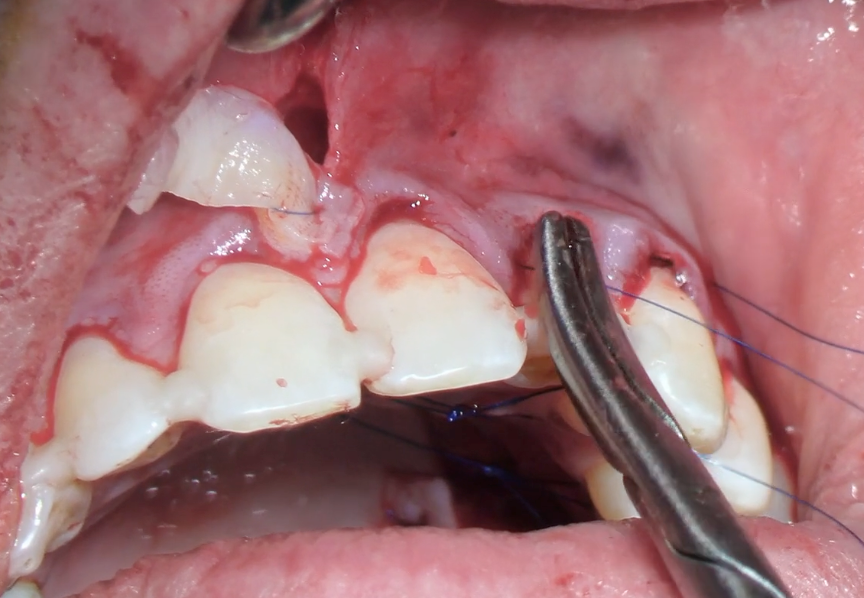

Technique opératoire étape par étape

Cette partie centrale détaille précisément la technique de tunnelisation, du design initial jusqu’aux sutures. À travers deux cas cliniques majeurs (maxillaire et mandibulaire), le participant visualisera chaque étape opératoire et comprendra comment adapter la technique aux différents sites. Une analyse des avantages, inconvénients et limites permettra de sécuriser et d’optimiser la pratique au quotidien.